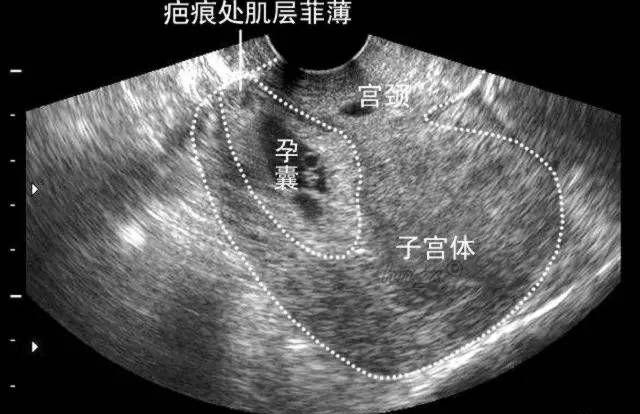

子宫瘢痕妊娠影响知多少,剖腹产后多久能做试管婴儿?

剖宫产术后再次怀孕,可能出现“子宫疤痕妊娠”,是一种特殊类型的异位妊娠。过去较为罕见,但近年来因剖宫产率居高不下,疤痕妊娠呈上升趋势。本病早期诊断困难,因漏诊导..

前次剖宫产,为什么做试管婴儿只给我移植1枚胚胎?

随着二孩政策的全面实施,很多夫妇多年的夙愿终于可能实现,越来越多的夫妇需要通过试管婴儿技术帮助他们实现愿望。一胎如果是剖宫产,那么诊断就多了一条:瘢痕子宫。今天..